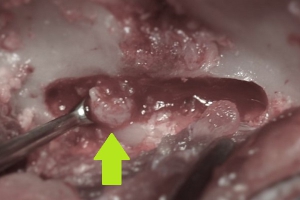

手術方法にはいくつかの方法があり、最も多く行われるのが、背中側から圧迫物質を除去して減圧する片側椎弓切除術や椎弓切除術、頸部の椎間板ヘルニアに対しては腹側(喉側)から行うベントラルスロット(腹側造窓術)が多用されます。いずれの方法も下の写真のように椎骨の一部に「窓」を形成して脊髄神経への圧迫を減圧して、飛び出した椎間板物質(黄緑矢印)を除去するということを基本とします。